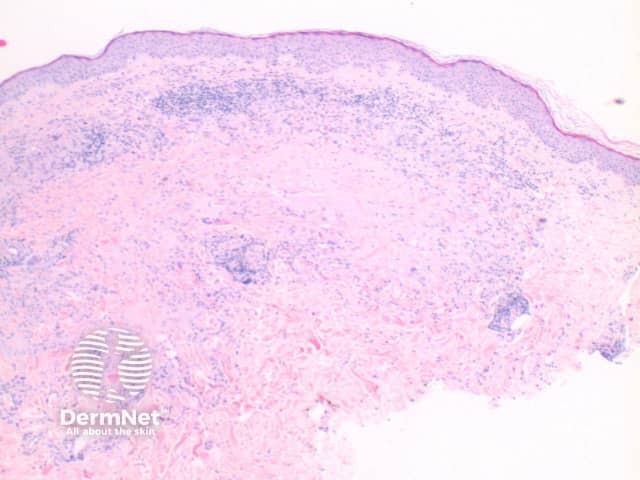

The histological features of bullous pemphigoid are:

Subepidermal bulla

Direct immune fluorescence